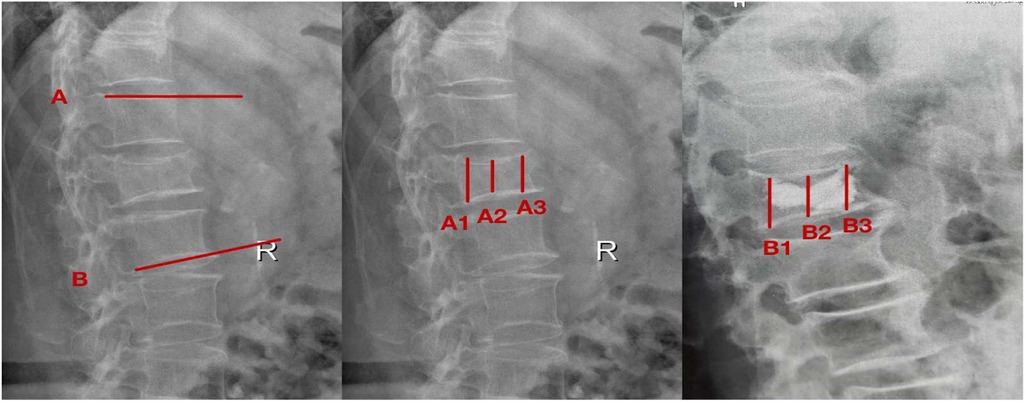

(1) The local kyphosis angle was calculated by measuring the angular intersection between two defined reference lines: Line A (drawn parallel to the superior endplate of the intact vertebra immediately cranial to the fracture) and Line B (positioned parallel to the inferior endplate of the adjacent intact vertebra caudal to the fracture), as illustrated in Figure 1.

(2) Postoperative radiographic evaluation included vertebral height measurement via plain films, assessing three parameters: (1) projected original height (determined from the mean of neighboring intact vertebrae), (2) pre-intervention fracture height [A2, calculated as the average of anterior [A3] and posterior [A1] border measurements], and (3) post-procedural restored height [B2, derived from anterior [B3] and posterior [B1] margin averages]. Height restoration percentage was computed using the formula: [(B2-A2)/projected original height] × 100%, as depicted in Figure 1.

Figure 1. Measurement of imaging parametersafter vertebroplasty. The reference lines were defined as follows: Line A runs parallel to the superior endplate of the intact vertebra immediately cranial to the fracture, while Line B parallels the inferior endplate of the adjacent intact vertebra caudal to the fracture. Preoperative measurements included: A1 (posterior vertebral margin), A2 (fractured vertebral height), and A3 (anterior vertebral margin). Corresponding postoperative measurements comprised: B1 (posterior margin), B2 (restored vertebral height), and B3 (anterior margin).